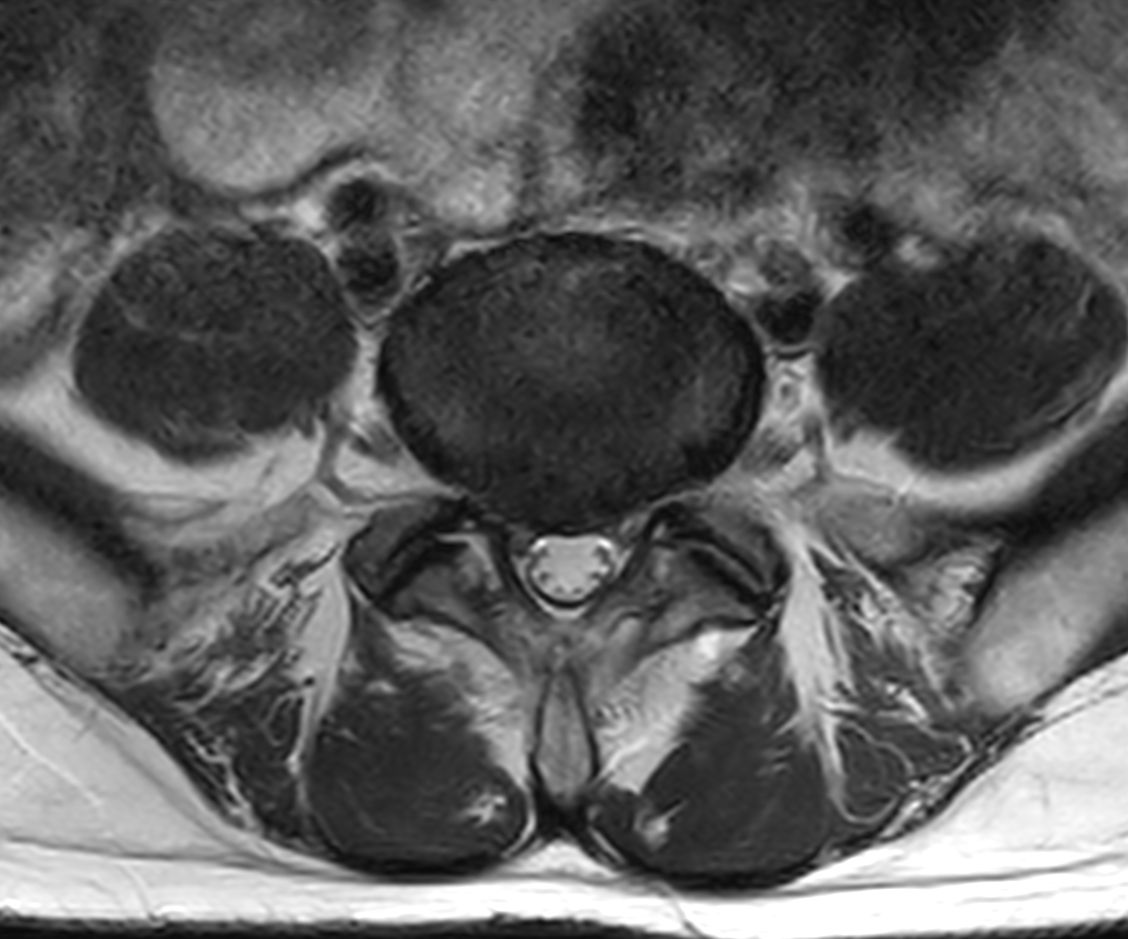

Total lumbar spine exam, showing excellent image quality in only 9:20 minutes.

Axial T2w TSE